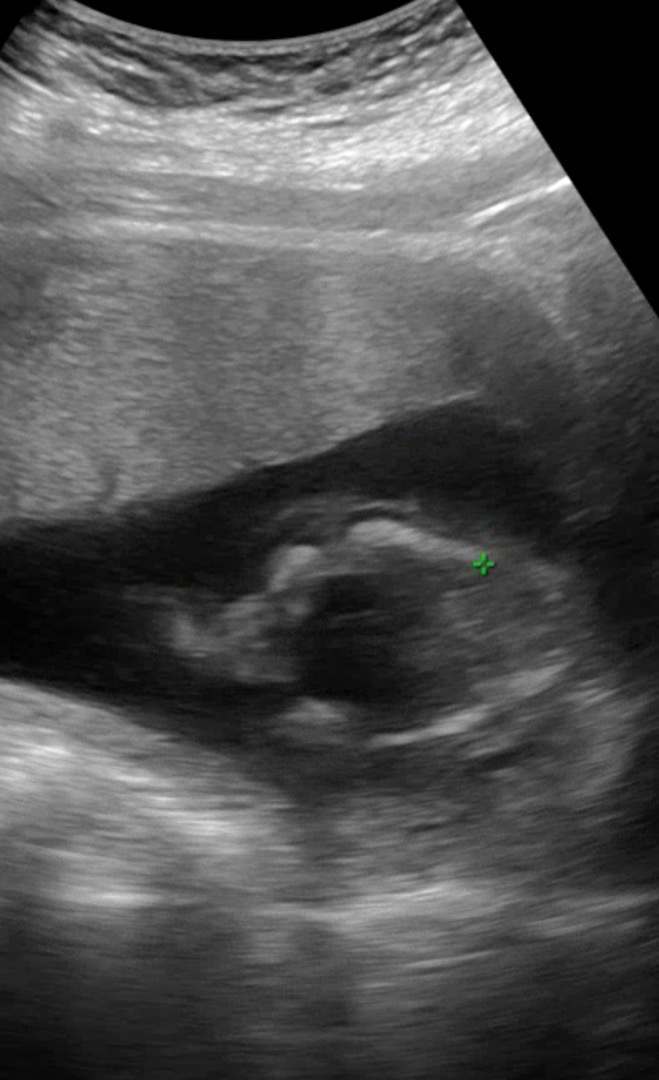

16주 초음파 성별 봐주세용!

초음파보고 왔는데 아들같은가용? 딸같은가요? 저는 아들같은데 의사선생님은 딸같다구 하시네요

제가 보기에도 딸같아요